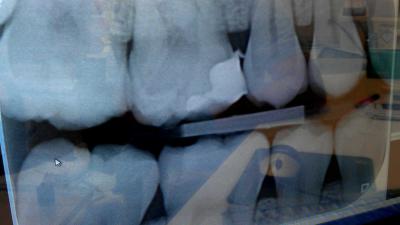

Dankzij 3D-beelden en 3D-geprinte mallen en implantaten, kunnen kaakoperaties accurater uitgevoerd worden. Dat concludeert technische geneeskundige Joep Kraeima